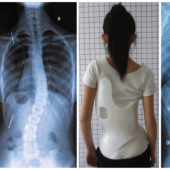

TLSO brace adalah korset tulang belakang kaku yang akan melindungi, menyembuhkan masalah pada tulang belakang toraks, lumbar, dan sakral. Hal ini digunakan untuk memberikan stabilisasi pasca-trauma dan pasca-bedah. TLSO brace yang dibuat khusus dan kaku memberikan kekuatan maksimum stabilisasi eksterior ke bagian tulang belakang yang toraks dan lumbar. Kisaran stabilisasi yang efektif adalah dari tulang… selengkapnya

Korset tulang belakang atau korset TLSO merupakan salah satu alat yang digunakan untuk menunjang suatu kelainan tulang punggung. Misalnya dikarenakan miring atau biasa disebut dengan skoliosis. Perlu Anda ketahui juga bahwa penggunaan korset yang satu ini adalah salah satu pilihan dan untuk seorang penderita skoliosis, karena dapat membantu mengecilkan derajat kelengkungan punggung seseorang penderita skoliosis…. selengkapnya

TLSO Brace – Pada saat Anda membicarakan tentang kelainan tulang belakang seperti skoliosis, ada dua faktor utama yang perlu dipertimbangkan yaitu pengurangan dan perkembangan. Pengurangan berarti benar-benar mengurangi kelengkungan secara struktural, dan perkembangan akan mengacu pada sifat kondisi menjadi lebih buruk, yang berarti kelengkungan semakin besar. Mencegah skoliosis menjadi lebih buruk adalah mungkin, tetapi hanya… selengkapnya

Rp 250.000MSO / Korset Scoliosis Kondisi tulang belakang bengkok merupakan kondisi kelainan pada tulang belakang, biasa disebut dengan kelainan scoliosis. Keadaan tulang belakang pada kelainan skoliosis dimana tulang belakang melengkung seperti huruf “C” atau “S”. dalam keadaan tulang belakang normal akan berbentuk seperti huruf “ I”. silahkan lihat pada gambar beriku ini. Penderita scoliosis biasanya tidak… selengkapnya